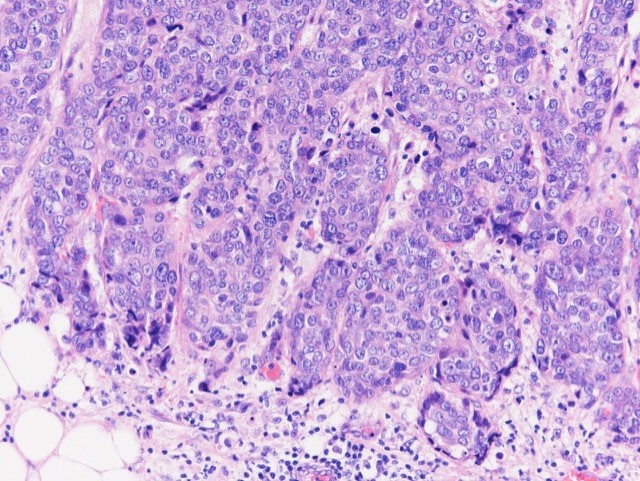

Microscopic (histologic) description

- Histological features of IBC NST vary considerably from case to case and even within the same case

- Margins vary from highly infiltrative, permeating the surrounding tissue, to continuous pushing margins

- Architecture varies from sheets, nests, clusters, cords or individual cells (but lacks the cytomorphological characteristics of invasive lobular carcinoma)

- Tubular formations are prominent in well differentiated tumors but absent in poorly differentiated tumors

- Variable cytological features:

- Cytoplasm may be abundant and eosinophilic but it can show other features in some tumors, including as clear, foamy or granular

- Nuclei may be regular and uniform or highly pleomorphic with prominent or multiple nucleoli

- Mitotic figures are variable from virtually absent to extensive

- 2 distinct growth patterns exist:

- Large and solid nests or syncytial infiltrative growth pattern with little associated stroma and an expansive growth that compresses the surrounding stroma (e.g., most basal-like breast cancers)

- Tumors characterized by small cancer nests accompanied by marked fibrosis (desmoplastic / scirrhous); this type diffusely infiltrates the surrounding tissue as an irregular shaped spiculated mass

- Calcification in 60% of cases, variable necrosis

- Elastosis involves stroma, wall of vessels and ducts and causes grossly noted chalky streaks

- Often ductal carcinoma in situ (DCIS) (up to 80%)

Microscopic (histologic) images

Contributed by Julie M. Jorns, M.D., Kristen E. Muller, D.O., Gary Tozbikian, M.D. and Emad Rakha, M.D.